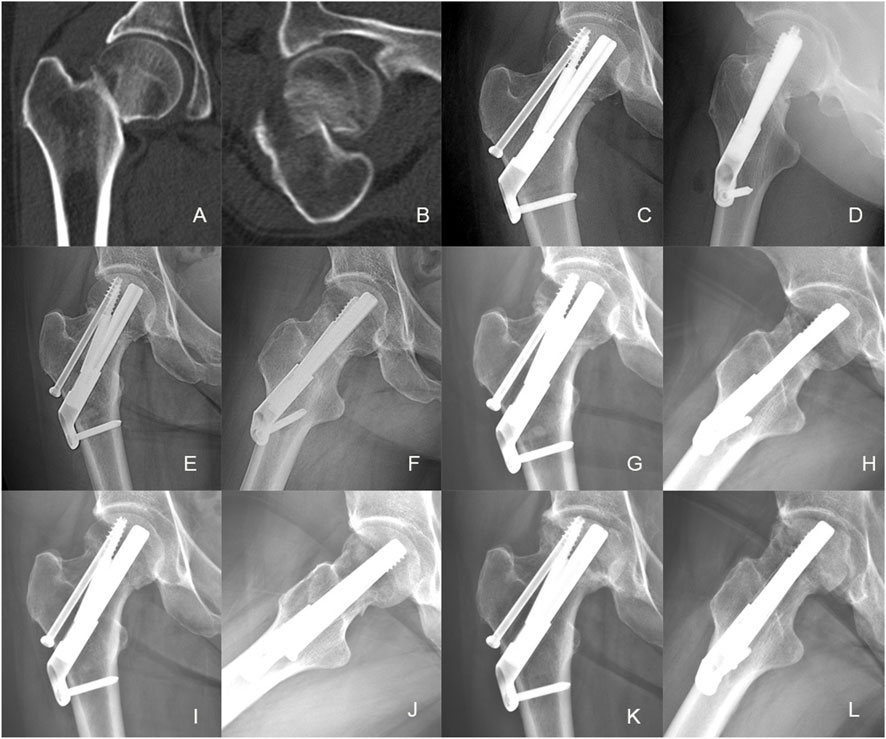

Background The purpose of this study was to explore the biomechanical property and clinical efficacy of femoral neck system (FNS) with an additional cannulated screws (CS) in the treatment of unstable femoral neck fracture (FNFs) with comminuted posteromedial cortex. Methods Firstly, we developed a model of Pauwels type III FNF with comminuted posteromedial cortex for the finite element analysis (FEA). Two experimental models were set up: the FNS model and the FNS+CS model. The von Mises stress on the proximal femur, implant and the total displacement of the device components were evaluated for both FNS and FNS+CS models. Secondly, we retrospectively included the cases of vertical FNFs with comminuted posteromedial cortex by FNS or FNS+CS fixation in our hospital from January 2020 to December 2023. In this study, demographic information, femoral neck shortening, Harris score of hip joint function, and postoperative complications were collected and compared. Results The FEA results showed similar peak von Mises stress of the implant in two models and the additional CS could share the stress concentration with the FNS in the FNS+CS model. In terms of proximal femur, the maximum von Mises stress of the FNS model increased by 15.43% when compared with the FNS+CS model, and the magnitude of these two models were 83.02MPa and 71.92 MPa, respectively. Furthermore, the maximum displacement in the FNS+CS model was much smaller than that in the FNS model. Clinically, the femoral neck shortening distance was significantly longer in the FNS group (5.62±3.32 mm) than that in the FNS+CS group (3.49±2.01 mm) (p = 0.027). Furthermore, the incidence of moderate to severe shortening (≥ 5 mm) was significantly higher in the FNS group compared with the FNS+CS group (p = 0.039). Moreover, the patients in the FNS+CS group had a higher Harris score than patients in the FNS group (91.97 vs. 88.56, p = 0.003). Conclusions Compared to the FNS alone, the FEA results showed that the FNS+CS had better biomechanical properties and the clinical results showed that the FNS+CS had a shorter femoral neck shortening and higher Harris score in treating unstable FNFs with comminuted posteromedial cortex.